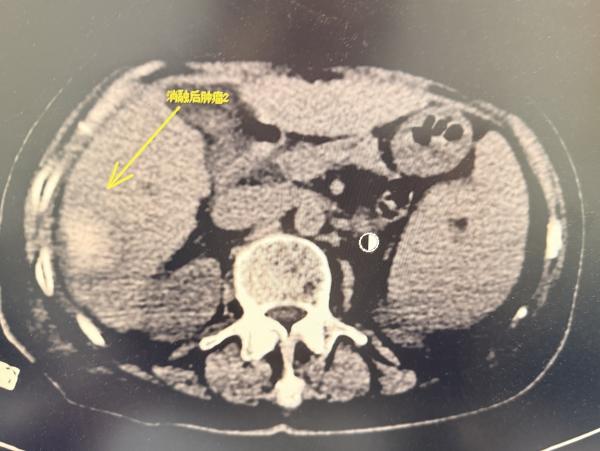

消融术前影像

术中,患者生命体征极度不稳定,血氧饱和度在70%至90%之间波动,呼吸急促导致消融针随膈肌大幅摆动,CT影像出现明显重影,为精准穿刺带来极大挑战。治疗过程中医生们沉着冷静、各司其职:麻醉科郭振海教授全程严密监护,精细调控呼吸与心率,确保能在血氧短暂回升至90%的宝贵窗口期内进针;陶冀教授团队则采取“阶梯功率、分次消融”策略,首轮以40-50-70W功率渐进消融9分钟后,调整针道进行第二循环治疗,最终完整覆盖两处紧贴肝被膜的病灶,肿瘤完全消融。历时2小时,手术顺利完成,患者未出现出血、气胸等并发症,术后生命体征逐步平稳,实现精准消融与安全治疗的双重目标。